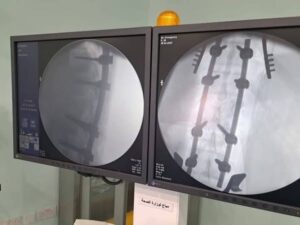

فقد تم اجراء عملية بغاية الخطورة من خلال تثبيت للعمود الفقري وتحرير النخاع الشوكي .

المريضه تبلغ من العمر 20 عاما” وهي تعاني من كسر في الفقرة القطنية الاولى غير مستقرة وضاغطة على النخاع الشوكي .